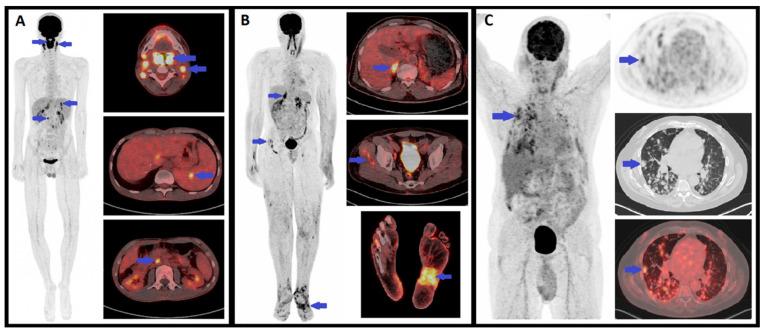

卡波西肉瘤(KS)是一种与免疫抑制相关的罕见非典型恶性肿瘤,可被视为一种机会性肿瘤,对免疫调节或恢复有反应。已确定有四种不同的流行病学形式(艾滋病相关型、医源性、地方性或经典型KS)。虽然临床检查足以诊断KS的皮肤病变,但为了检测累及其他器官的病变,还需要进行额外的检查。近年来,已开发出新的组织学标志物用于检测病变中HHV-8潜伏或裂解蛋白,在临床诊断存疑时有助于确诊。最近,局部免疫反应的评估也已显示在必要时为选择合适的治疗方案提供一些指导。我们还综述了传统放射影像学以及诸如F-氟脱氧葡萄糖正电子发射断层扫描、热成像和激光多普勒成像等非侵入性成像工具在KS诊断及需要全身治疗患者的治疗反应随访中的应用指征和结果。